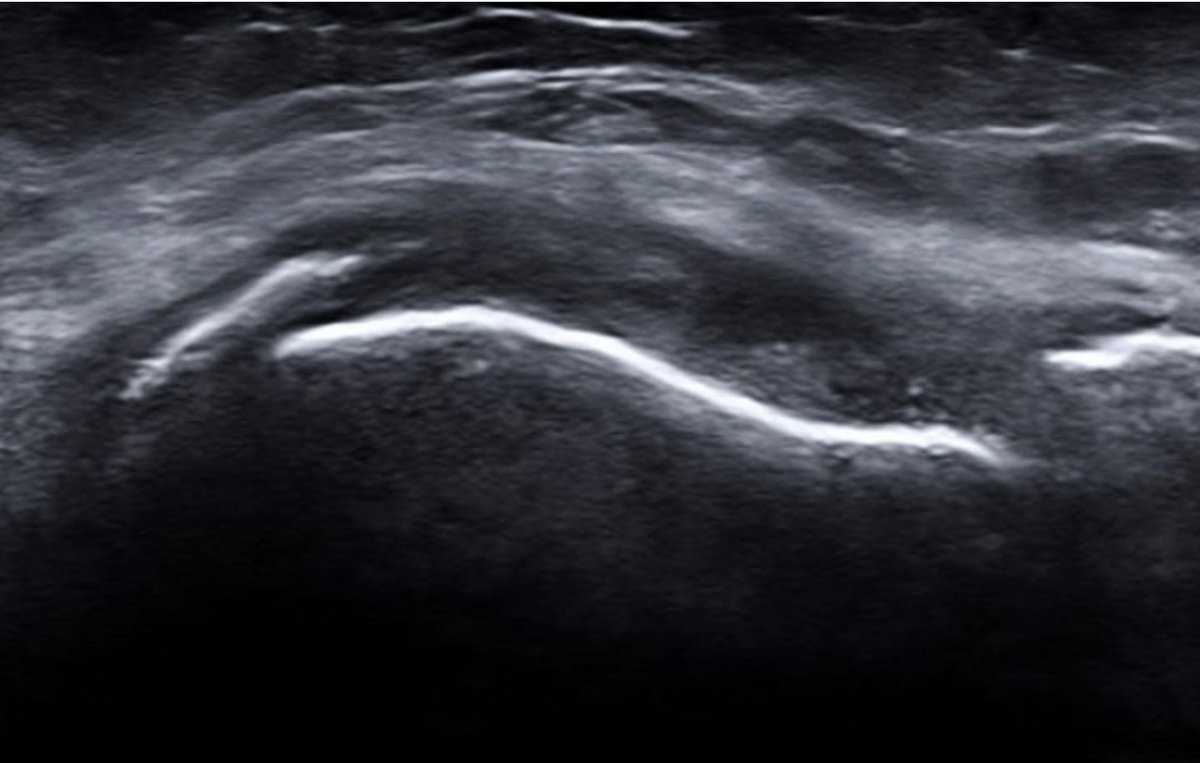

US- astericks = inflammation; PD hyperaemia